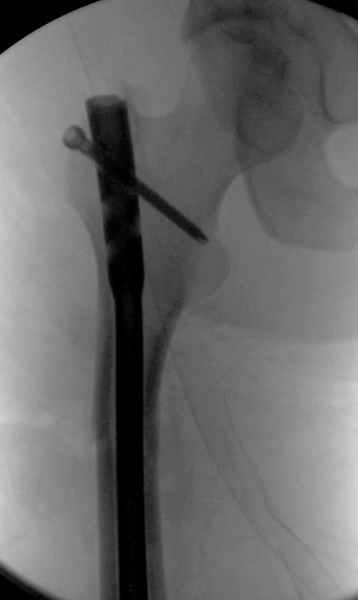

Как раз недавно у меня был примерный случай: больному 36 лет, поступил ночью, травма в результате мотоциклетной аварии, кроме чрезвертельного и спирального перелома левого бедра имеется переломы костей предплечья с этой же стороны. Скелетное вытяжение, а на следующий день больной про оперирован на ортопедическом столе с дистракцией. Чтобы не расколоть чрезвертельный перелом провели временную спицу ближе к переднему кортексу, из малого разреза костодержатель для репозиции, а фиксацию провели антиградным штифтом. Этапы операции на снимках.

Джолдас Кульджанов